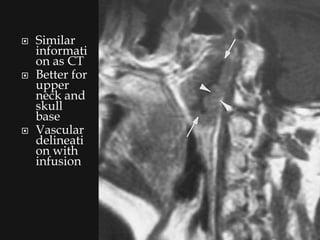

   Similar

informati

on as CT

   Better for

upper

neck and

skull

base

   Vascular

delineati

on with

infusion

Similar informati on as CT  Better for upper neck and skull base  Vascular delineati on with infusion